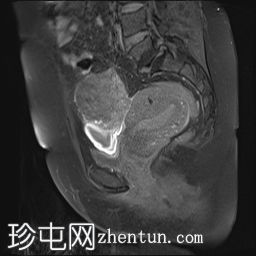

冠状位

T2加权像

可见子宫外腹腔内妊娠囊,内含胎儿组织。

该妊娠囊向后推移子宫,并与剖宫产瘢痕凹陷处紧密相连。

该妊娠囊与相关肠袢无法分离。可见其与性腺血管密不可分,且性腺血管明显突出。

胎盘位于妊娠囊后方,紧贴子宫前壁。

沿妊娠囊下缘可见一处异质性局灶性积液,最大轴向尺寸约为 8.4 × 5.5 cm,T1 加权像呈异质性高信号,T2 加权像呈异质性中等信号,T1 脂肪抑制序列未见信号下降,提示为血液成分。该积液压迫膀胱。

可见周围脂肪间隙呈条索状改变。

子宫体积增大,后倾,子宫内膜厚度约 1 cm,子宫下段前壁可见局灶性变薄(既往子宫瘢痕)。子宫连接区完整,未见肌层肿块。可见子宫内膜腔边缘有血性分泌物。